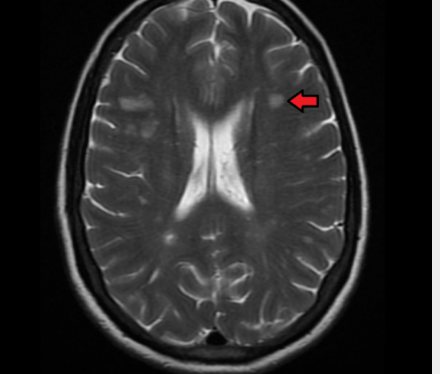

多发性硬化症是一种脱髓鞘疾病,其特征是大脑神经细胞绝缘层受损。多发性硬化症没有已知的治愈方法,长期结果也难以预测。MS是影响中枢神经系统的最常见的免疫介导疾病,全世界有2-250万人患有这种疾病。现在,UCL领导的一项新研究发现,早期MRI扫描可用于预测疾病的进展。

科学家们发现了164名患有临床孤立综合征(CIS)的人,并对他们进行了15年的跟踪调查。CIS患者通常也会继续患有MS。经过15年的研究,科学家们找到了参与者并评估了他们的残疾程度。57%患有复发型多发性硬化症,15%患有继发性进展型,27%仍患有CIS,1%患有其他疾病。研究人员查看了这些人在长期研究期间收集的MRI,发现早期脊髓损伤表明患者更有可能继续发展为继发性进行性多发性硬化症。换句话说,MRI分析允许预测每个参与者未来的残疾水平。

能够准确预测MS的进展极为重要。这有助于制定更有效的治疗计划,而且患者自己也知道他们在不久的将来可以期待什么。大量研究表明,早期强化治疗可带来更好的MS预后。然而,当你不知道会发生什么时,做出这样的决定是很困难的。MRI测试可以帮助使这些预测准确。